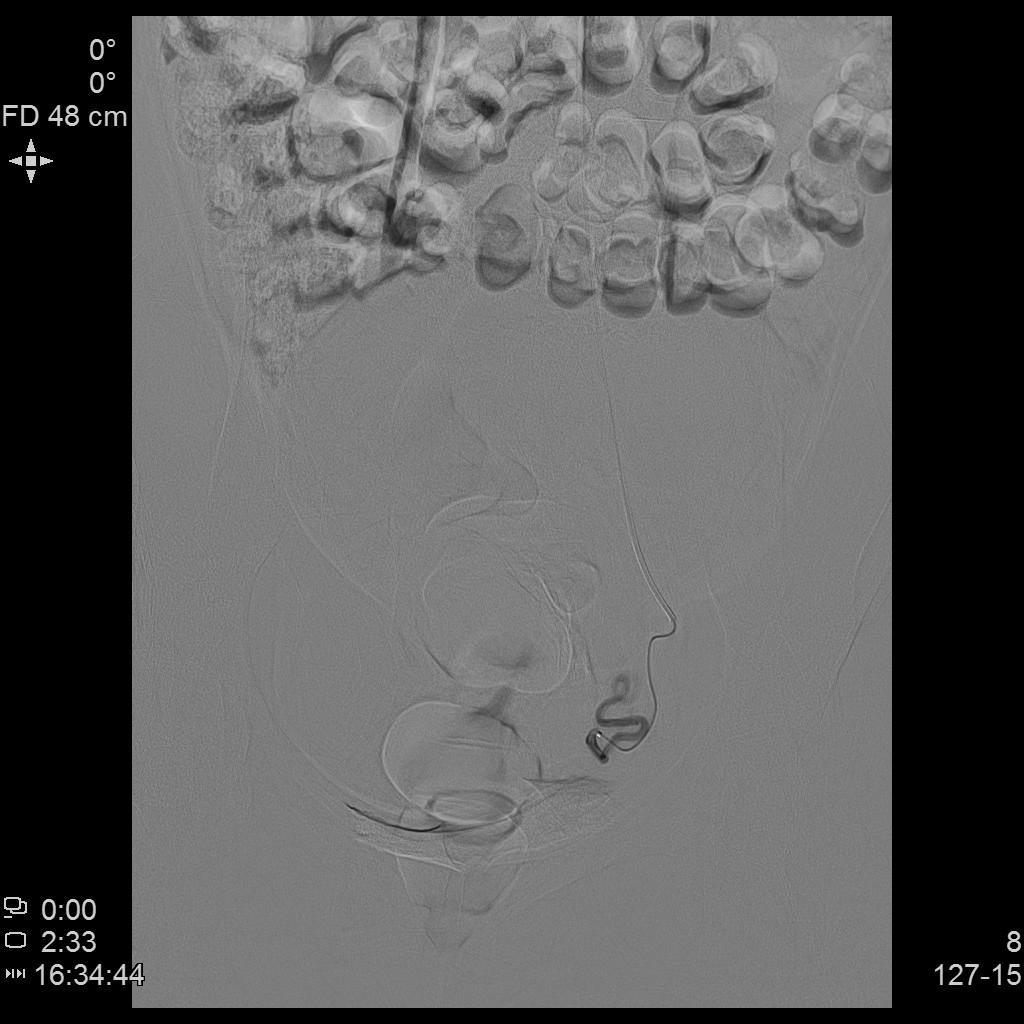

- 进一步超选插管右侧髂内动脉造影确认子动脉开口位置。

右侧髂内动脉造影

- 进一步超选插管左侧髂内动脉造影确认子动脉开口位置。

左侧髂内动脉造影

- 术后桡动脉止血器压迫止血8小时,患者术后无需长时间卧床、下肢制动,舒适度大大提升,利于术后快速康复。

桡动脉压迫止血器